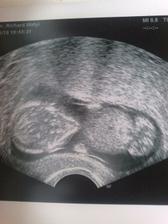

na 8DPO som bola nedockava a spravila som si testik, kde som nasla dusika..tesila som sa s neho aj ked som nevedela co najdem zajtra ...lenze kazdym dnom ten dusik silnel a silnel a my sme naozaj uverili tomu , ze po dlhych 12 mes. znova cakame nase vytuzene a vymodlene babo....v kutiku verime, ze to bude chlapcek ale nasa radost je tak obrovska , ze sa potesime comukolvek :O)

@flamenga daujem....je cely tato :O) a ma aj naozajstny pipik :O)))))))))